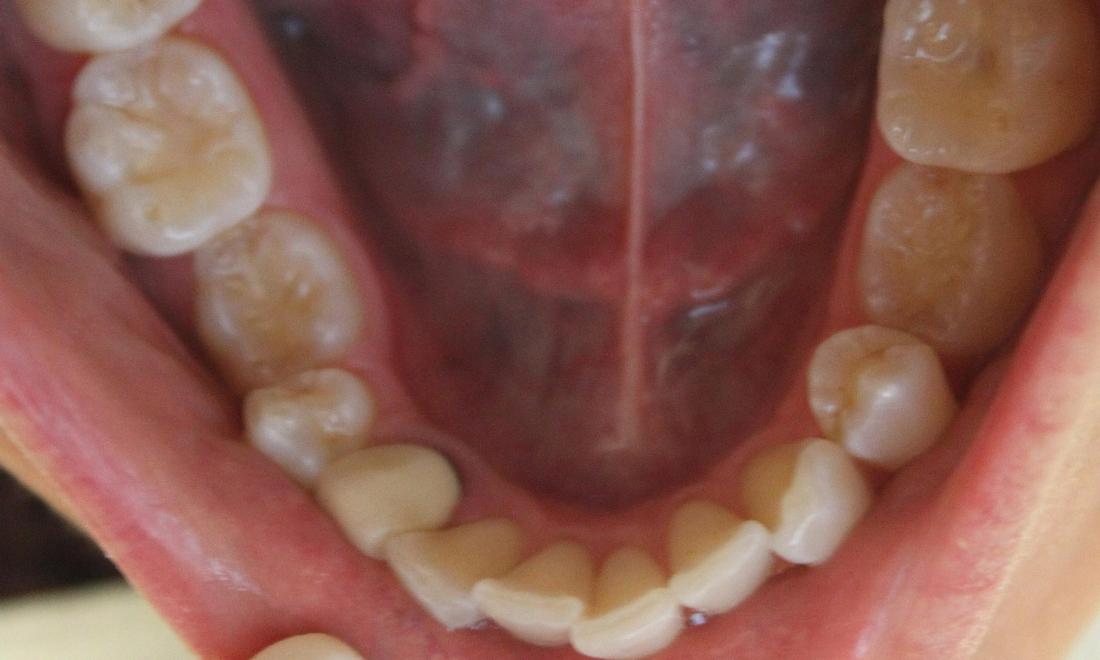

Crowding-- Some potential issues: Buildup of plaque and tartar, harbors harmful periodontal bacteria, risk of periodontal disease, tooth, and bone loss. After one year of Invisalign treatment, teeth have aligned properly for a healthier mouth.

crowded lower front teeth | invisalign dentist vienna lower front teeth after invisalign | dentist in vienna va